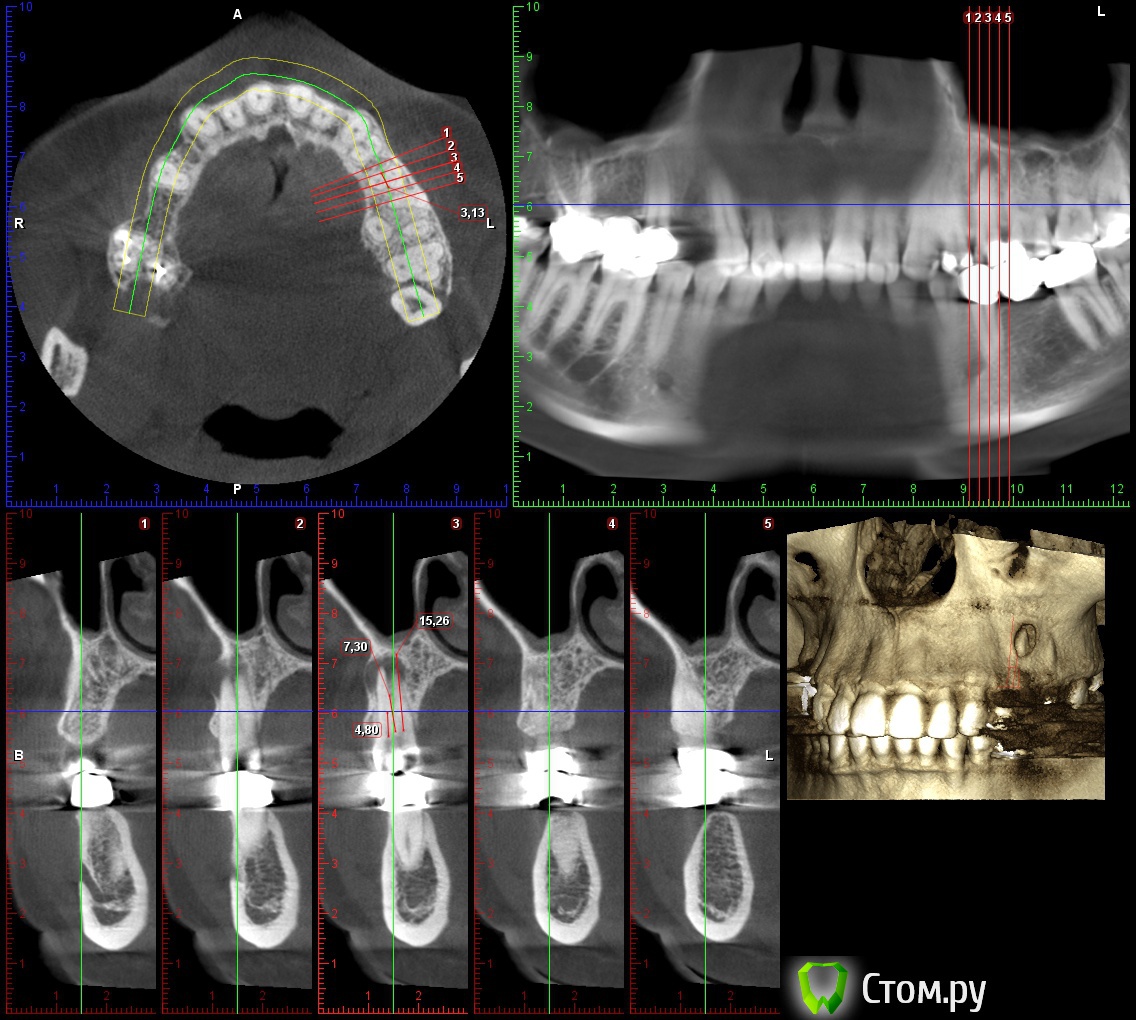

lonely_jack Опубликовано 19 февраля, 2014 Поделиться Опубликовано 19 февраля, 2014 Всем доброго времени суток Принесли КТ для планирования имплантации в области 14 зуба, а там...В области 25 явно напрашивается цистэктомия ( ну и как я думаю удаление 25)... Отсюда пару вопросов:1. Возможность одномоментной имплантации? (естественно с графтом и мембраной)2. Нужно ли на гистологию? (сам думаю, что нет)3. В области 26 и 27 также имеются разрежения (срезы одинаковые, поэтому выкладываю только 26), но с корнями вроде бы не контактируют. Это рисунок кости или все таки стоит насторожиться? Ссылка на комментарий